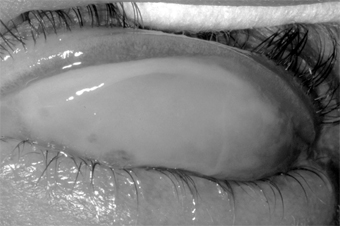

Epidemic keratoconjunctivitis is usually bilateral. The onset is often in one eye only, however, and as a rule the first eye is more severely affected. At onset the patient notes injection, moderate pain, and tearing, followed in 5-14 days by photophobia, epithelial keratitis, and round subepithelial opacities. Corneal sensation is normal. A tender preauricular node is characteristic. Edema of the eyelids, chemosis, and conjunctival hyperemia mark the acute phase, with follicles and subconjunctival hemorrhages often appearing within 48 hours. Pseudomembranes (and occasionally true membranes) may occur and may be followed by flat scars or symblepharon formation (Figure 5-5).

Figure 5-5: Epidemic keratoconjunctivitis. Thick white membrane of upper palpebral conjunctiva.

The conjunctivitis lasts for 3-4 weeks at most. The subepithelial opacities are concentrated in the central cornea, usually sparing the periphery, and may persist for months but heal without scars.